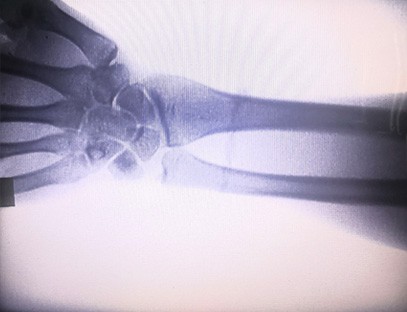

A X-ray of Extremities rendszer egy speciális radiográfiai rendszer, amelyet a végtagok csontjairól és ízületeiről készítenek, beleértve a karokat, lábakat, kezeket és lábfejeket. A rendszert úgy tervezték, hogy tiszta és pontos képet adjon a végtagok csontjairól és ízületeiről diagnosztikai célokra. A berendezés sokoldalú, könnyen használható, és számos ortopédiai és sportorvosi állapot diagnosztizálására használható.

1. Tiszta és pontos képek: Termékünk tiszta, éles és nagy felbontású képeket készít, amelyek lehetővé teszik az orvosok számára, hogy soha nem látott pontossággal értékeljék az ízületek, csontok és más testszerkezetek állapotát.

4. Sokoldalú: Termékünk számos állapotot képes diagnosztizálni, például ízületi gyulladást, töréseket, daganatokat és egyéb, a végtagokkal kapcsolatos rendellenességeket. A rendszer a képalkotási lehetőségek széles skáláját kínálja, mint például állva, ülve vagy fekve, hogy pontos diagnózist készítsen, amely megfelel a különböző betegek igényeinek.